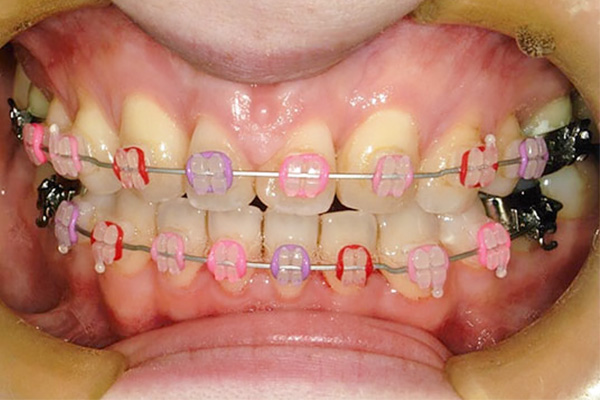

1年3ヶ月後